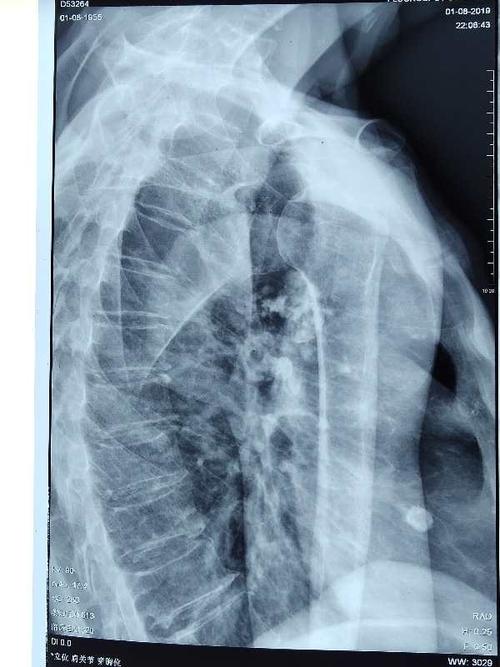

肩关节穿胸位x线摆位

肩关节穿胸位x线摆位,肩关节穿胸位x线图片

肩关节穿胸位x线图片

肩关节穿胸位标准片

肩关节穿胸位片

肩关节穿胸位

x线肩关节穿胸位拍法

肩关节穿胸位x线

肩关节穿胸侧位摆位

肩关节穿胸侧位

肩关节穿胸位示意图

肩关节穿胸位片图片